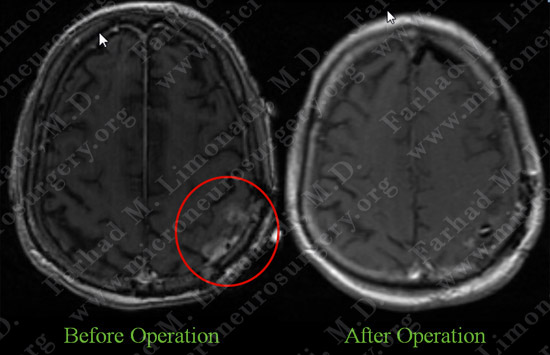

Post-op Imaging

Post-op MRI shows complete resection of both tumors with no injury to surrounding neurovascular structures.